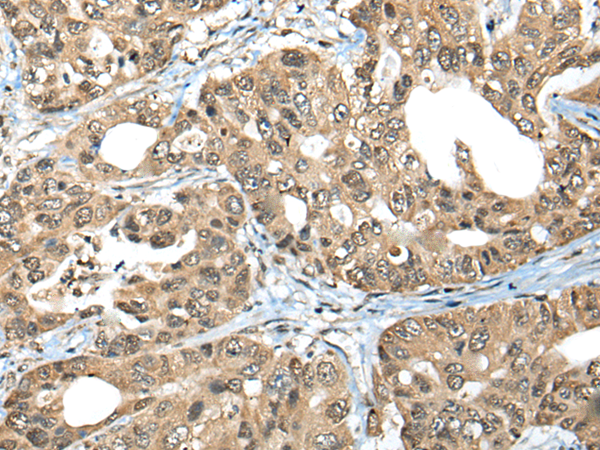

Product Image

The image is immunohistochemistry of paraffin-embedded Human gastric cancer tissue using (ZNF468 Antibody) at dilution 1/35. (Original magnification: ×200)